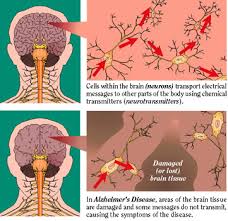

La enfermedad de Alzheimer es la forma más común de demencia. En el parénquima cerebral coexisten ovillos neurofibrilares intraneuronales, depósitos de amiloide extracelulares en forma de placas amiloides, angiopatía amiloide cerebral, y pérdida sináptica y neuronal, siendo las áreas límbicas las más severamente afectadas.

lo que sugiere que ambas enfermedades pueden proceder de mecanismos de plegamiento similares. Una presentación de los caminos patogénicos comunes asociados con estos trastornos, incluyendo mecanismos de muerte celular, la producción de especies reactivas de oxígeno, la disfunción mitocondrial y anomalías vasculares, servirán como un punto de inicio para posteriores estudios.